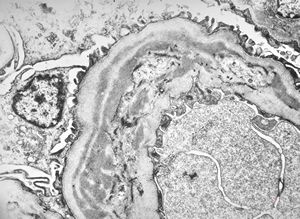

F,14y. | Alport syndrome - split and laminated, thick/thin basement membranes